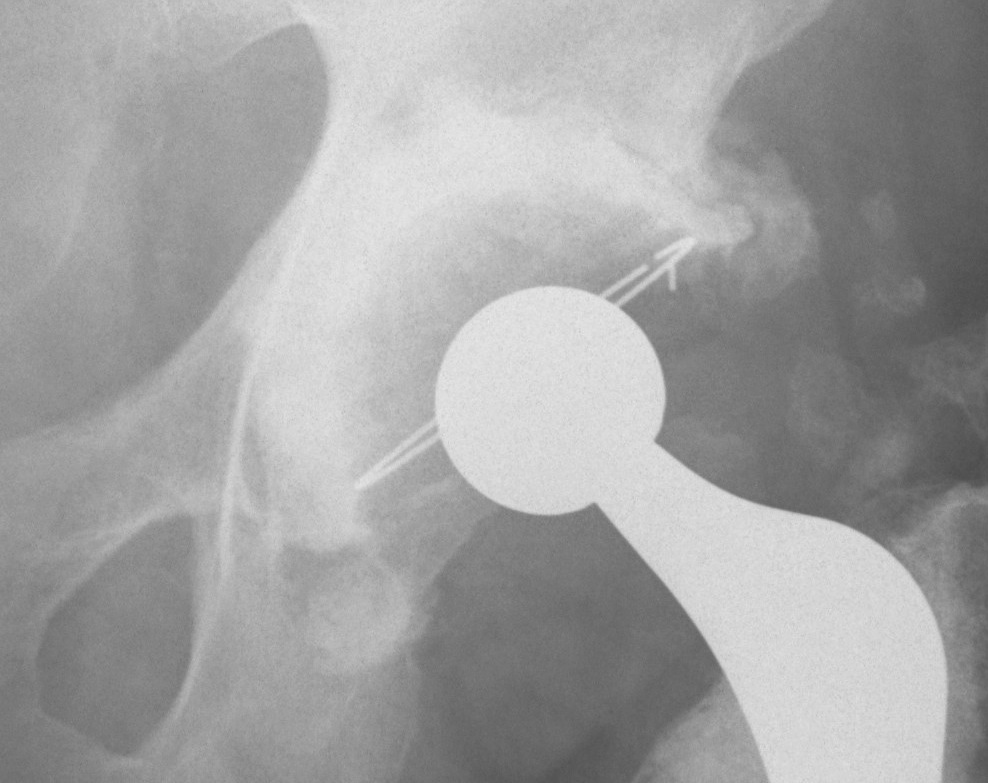

Cement

Inferior cement Inferior cement Intra-pelvic cement